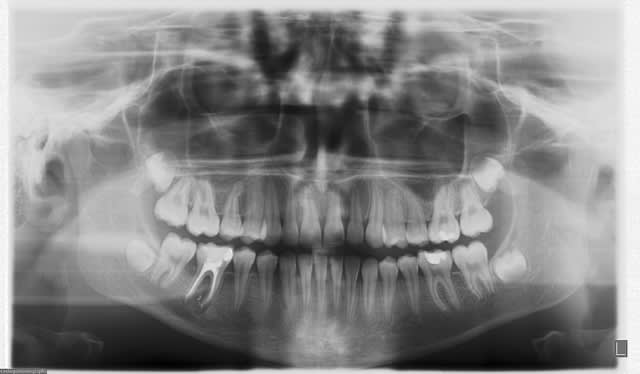

> Un exemple parmis d'autres...

> 2e essai

alors la c'est notre ben qui va etre jaloux!!!